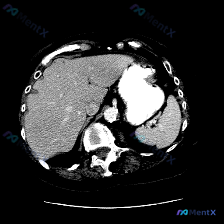

今天整理了一个很有警示意义的影像病例,核心是单张平扫CT下的脾脏病变,想和大家一起梳理下完整的分析思路。 先看影像核心发现 - 定位:上腹部CT软组织窗,左侧脾脏层面 - 关键异常: 1. 脾脏肿大; 2. 脾实质内见大范围、边界尚清晰但密度不均匀的低密度影,形态呈相对弥漫或片状,主要占据后部及部分...

今天整理了一份上腹部增强CT的影像资料,结合临床分析思路,觉得挺有讨论价值的,分享给大家。 影像核心发现 上腹部增强扫描(软组织窗): - 肝脏:轮廓光滑,密度均匀,未见明确局灶性病变; - 脾脏:体积增大,实质内见多发圆形/类圆形低密度灶,边界相对清晰,增强后无强化或强化程度远低于正常脾实质; -...

今天整理了一张很有启发的上腹部CT平扫影像,核心发现是脾脏内的多发类圆形低密度灶,想和大家一起梳理一下鉴别诊断的思路。 --- 先看影像的客观表现 这是一张上腹部横断面CT平扫(软组织窗): - 肝脏:形态大小、实质密度都还好,没看到明确占位,肝门血管也清晰; - 脾脏:是最显眼的地方——多个类圆形...